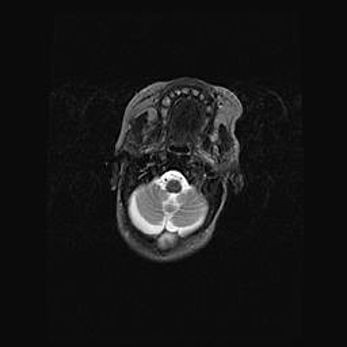

Подострая гематома правой гемисферы мозжечка.

Наружная гидроцефалия.

Возраст: 15 дней

Вес: 3100 г

Пол: женский

Окружность головы: 37 см

Срок гестации: 35-36 недель

При открытой наружной форме гидроцефалии у новорожденных расширяются и переполняются субарахноидные пространства.

Кровоизлияния в мозжечок имеют две клинико-анатомические формы: полушарные гематомы и кровоизлияния в червь.

К появлению этой патологии может привести: повреждения головного мозга, возникающие в результате асфиксии и гипоксии плода при беременности, или травмы во время родов. Редко гематома мозжечка может быть результатом первичной коагулопатии и сосудистой мальформации, диссеминированном внутрисосудистом свертывании, изоиммунной тромбоцитопении.